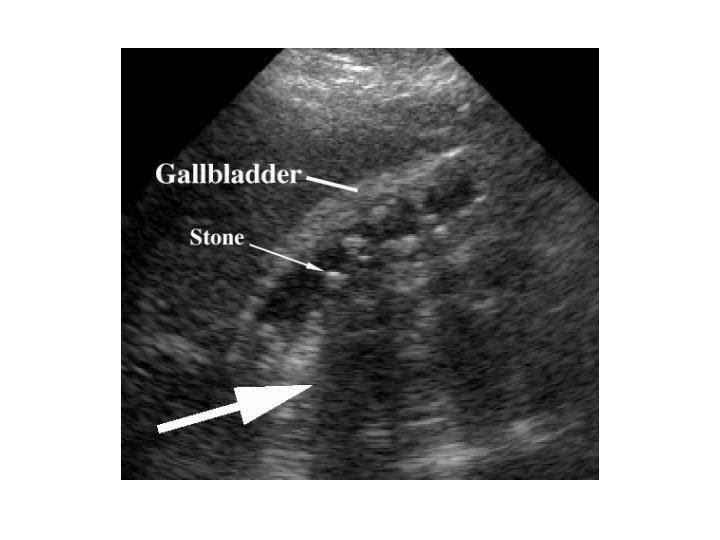

Gallbladder Cancer Ultrasound

Gallbladder Cancer Ultrasound Can Upper Endoscopy Detect Gallbladder Problems Abdominal ultrasound, endoscopic ultrasound, ct scan or magnetic resonance cholangiopancreatography can make pictures. Ercp helps diagnose and treat problems that affect the liver, pancreas, gallbladder and bile ducts. Endoscopic retrograde cholangiopancreatography (ercp) used to see inside the main bile duct shared by the pancreas and gallbladder and take tissue samples for biopsy. The most common symptom of gallstones is abdominal. Can Upper Endoscopy Detect Gallbladder Problems.